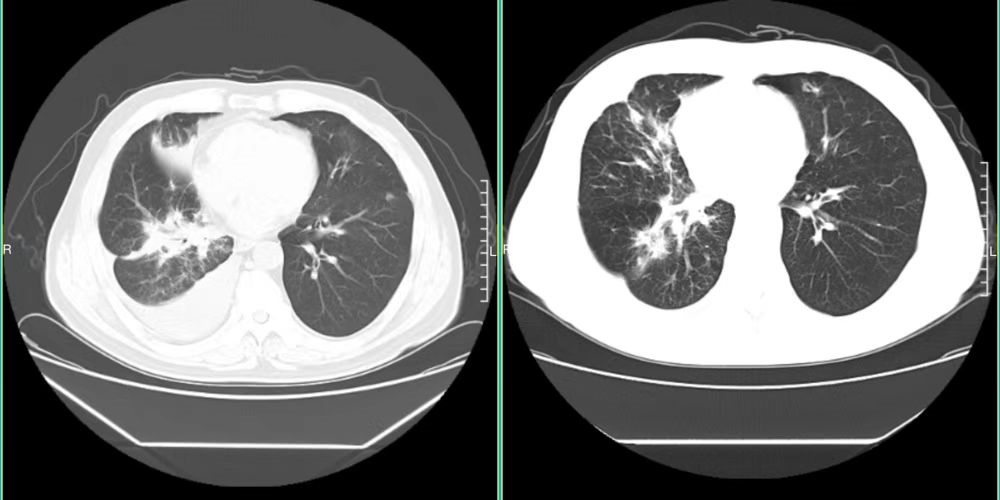

下面是我截的对比图,左侧是当时最严重时的片子

回家后,我把郑州医生的治疗意见告与我家医生听,我家医生比较担心白紫的副作用,我们决定先穿刺,再次做基因检测,穿刺时我家医生亲自去看ct引导,此时距离上次拍ct15天,但可以看到已有进展,肺部云雾状的东西增多了,我们立即决定开始吃安罗替尼。并在下个周期开始用上白紫。期间我们第二次做的基因检测结果出来了,这一次做的全套检测仍然无常规基因突变,KRAS G12V突变丰度25.24% TP53突变,肿瘤突变负荷(TMB)4.7muts/Mb 较低微卫星稳定型(MSS),PDL1表达率60%,仍然是高表达,这也给我了我们些继续用PD1的信心。

2022年3月28号,停药失败了,免疫性相关肺炎也可以排除了。肿瘤标志物之前从来都是正常的,现也成倍增高。ct上,右侧大量的胸腔积液,右肺大面积的炎症伴肺实变。每多看一次,我的心就扎一次。我明白,这次是个大坎。我立马去郑大一附院挂号,当时有几位医生已明确的告诉我,再用药也不一定会有你想要的效果,只能是尝试,甚至有医生直接告诉我一个月的生存期。

2022年5月16号,ct报告显示右肺下叶类结节较前缩小,右肺炎性改变伴局部肺实变较前缩小,右侧胸腔积液较前缩小,肿瘤标志物全部回归正常(泪奔...)我赶紧给晶晶医生发了短信,报了平安。

2022年6月6号,ct报告显示右肺下叶类结节较前继续缩小...肿瘤标志物都在正常范围内。